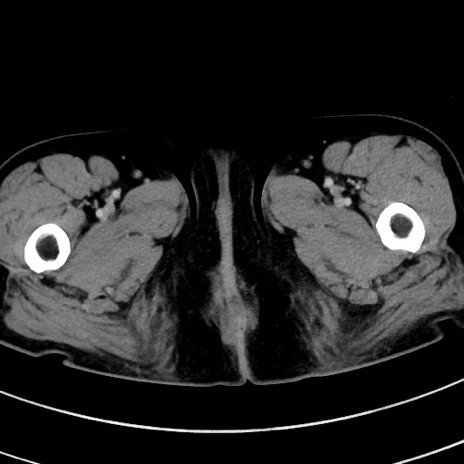

症例9(横断像)

【症例】 60歳代女性

【主訴】むかつき、みぞおちの痛み

【現病歴】3日前よりむかつきがあり、食事がとれない。

【既往歴】糖尿病

【身体所見】発熱なし、心窩部圧痛軽度あるも、腹膜刺激症状なし。

【データ】WBC 7400、CRP 1.92